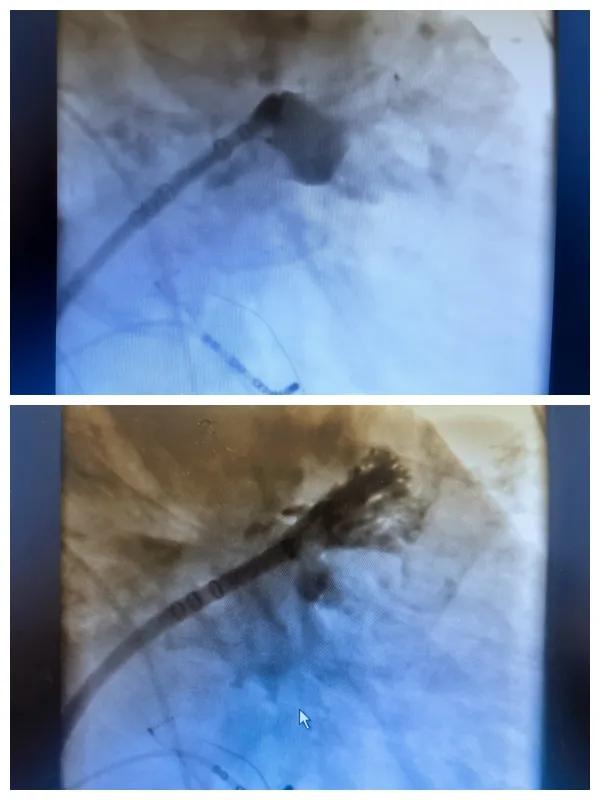

漯河市二院成功開展房顫射頻消融術+左心耳封堵WM FLX一站式手術,再攀“心”高峰!

6月26日,市二院成功為一名老年房顫患者實施了房顫射頻消融術+左心耳封堵WM FLX一站式介入治療,標志著醫院在心律失常介入治療領域邁出了嶄新的一步,開啟了新的治療篇章。

本次手術特邀我國著名心血管內科專家、河南省胸科醫院黨委書記袁義強及血管內科七病區主任黃瓊教授蒞臨指導,市二院院長王瑾帶領心血管內科電生理等專家團隊緊密合作,一次性解決了患者房顫、血栓兩大困擾,也使患者告別了終身服用抗凝藥的痛苦,極大地降低了患者的經濟和用藥負擔。

為了讓患者得到全面、綜合的治療,經過團隊術前充分討論,并征得家屬同意,心血管內科團隊決定采用目前國內外先進的房顫射頻消融術+左心耳封堵WM FLX一站式介入微創手術來治療老人的疾病。整個手術過程圓滿順利,術后何大爺各項體征正常,蘇醒后順利返回病房。